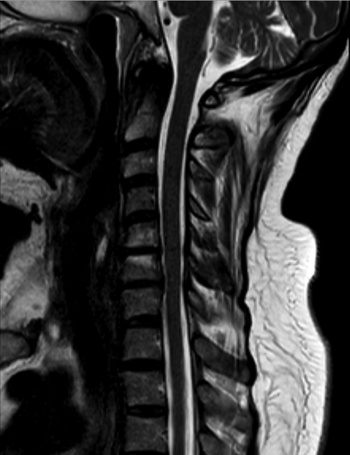

Az ionizáló sugárzással nem járó magnetikus rezonancia (MR) vizsgálat szintén közkedvelt képalkotó eljárás prospektív ikervizsgálatok esetén (3. a, b ábra). Számos területen, főleg a neuroradiológiában alkalmazzák ikrekben. Egyik MR kutatási terület a diffúziós tenzor képalkotás (DTI), melynek során azt vizsgálják, milyen mértékben befolyásolják a genetikai tényezők az agyi kapcsolatokat különböző agyi területeken. A DTI-rekonstrukcióból származó frakcionált anizotrópia tizenegy nagy fehérállományi pálya esetében nagyon örökletesnek bizonyult (Kochunov et al., 2015). Az MR-vizsgálat a T1-szekvencián magas jelintenzitást mutató zsírréteg megítélésére is kiválóan alkalmas. Ezt használták ki egy ausztrál ikervizsgálat során, ahol MR segítségével kapcsolatot mutattak ki az alacsony születési súly és az emelkedett zsigeri, illetve szubkután zsírszövet térfogata között, ami azt jelenti, hogy zsigeri és hasi elhízásra nagy kockázatot jelent az alacsony születési súly (Hng et al., 2006), mely összhangban van az epigenetikai tanulmányok eredményeivel, hiszen ez a várandósság alatti kóros programozódást tükrözi. A finn ikerkutatók obezitás-diszkordáns egypetéjű ikerpárokon végeznek vizsgálatokat. Olyan egypetéjű ikerpárokban, akik hosszú távon a fizikai aktivitásban különböznek, MR-vizsgálattal kimutatták, hogy a rendszeres fizikai aktivitás fontos tényezőnek számít a magas rizikójú zsírszövetek lerakódásának megelőzésére, még akkor is, ha a genetikai meghatározottság és a gyermekkori környezeti tényezők állnak a legtöbb antropometriai paraméter, például a testzsír, BMI, testsúly stb. hátterében (Leskinen et al., 2009). Ezt igazolja a fizikai aktivitás által kiváltott epigenetikai módosulás, a hisztonkód átrendeződés, valamint a PGC-1α génmetiláció dózisfüggő csökkenése. A magas rizikójú zsírszövet felszaporodásának adverz hatásait egy fizikai aktivitásra diszkordáns egypetéjű férfi ikerpáron mutatták be. Azonos foglalkozásuk mellett az aktívabb iker rendszeresen futott, míg inaktív ikertestvére ülő helyzetben töltötte legtöbb idejét, így MR-rel igazolva 74%-kal több viscerális, 150%-kal magasabb az intramuszkuláris és 63%-kal magasabb szubkután zsírszövettel rendelkezett, s szintén összefüggést találtak a máj és a pankreász zsírtartalma, illetve az inzulinrezisztencia között (Hannukainen et al., 2011).

3. a, b ábra. Egy 64 éves egypetéjű magyar ikerpár két tagjának (A: elsőszülött, B: másodszülött) nyaki gerinc MR-vizsgálata (T2-szekvencia), melyek hasonló mértékű degeneratív eltéréseket mutatnak